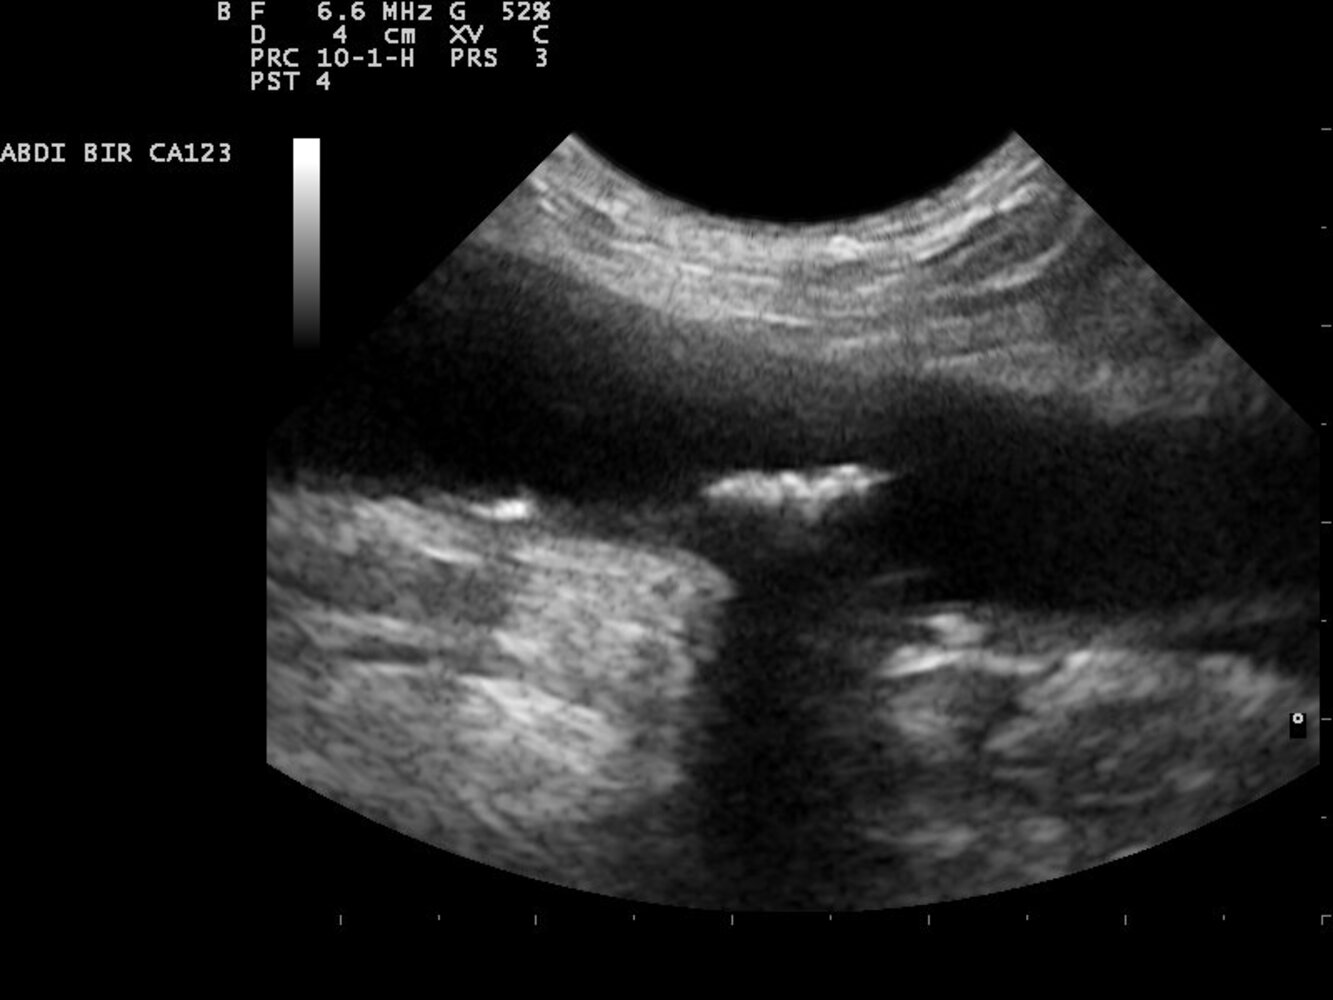

- Abdominal aortic aneurysm, thoracic aortic aneurysm

- Weakening of vessel wall: arterial aneurysm or dissection (e.g., aortic aneurysm, aortic dissection)